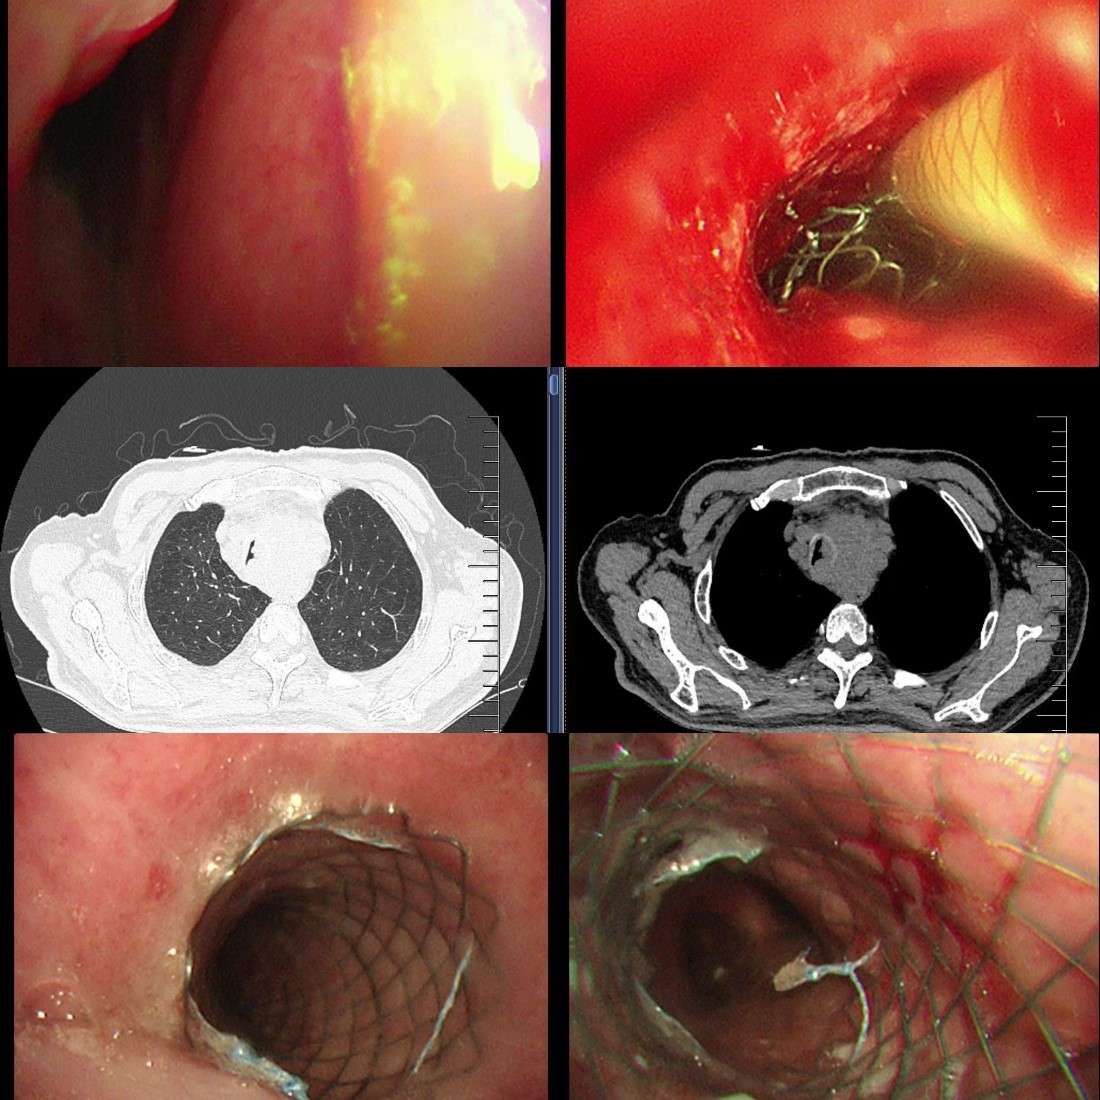

出院后,龚先生在苏大附四院肿瘤科接受了放疗(食管肿瘤灶及转移淋巴结)、替雷利珠单抗免疫治疗联合替吉奥口服化疗,8月复查时虽提示纵隔占位增大、局部压迫食管气管,但整体状态尚可。然而,9月中旬,他再次突发胸闷气喘,此时的龚先生虽神志清楚但精神极差,饮食睡眠受严重影响,不能平卧。龚先生被紧急送至我院急诊,收住入院,患者在无创呼吸机辅助下仍呼吸急促、呼吸窘迫。蒋军红主任团队为其紧急手术治疗,在手术室气管镜镜下景象触目惊心:原支架上端新生物已几乎完全阻塞气道,狭窄程度接近95%,且伴有活动后出血,随时可能因血块堵塞或缺氧危及生命。

蒋军红主任团队冷静制定策略:使用APC(氩等离子凝固术)对新生物进行局部消融,减少阻塞,稀释肾上腺素、冰盐水止血,随后快速的在原有支架腔内最狭窄部位,精准叠加置入一枚12×30mm金属裸支架。操作过程顺利,术后支架通畅度显著提升,远端管腔无明显狭窄,同步留取灌洗液送检明确感染与肿瘤情况。

术后,龚先生间断出现咯血,团队加强止血治疗后症状好转;因食管狭窄严重无法进食,联合介入科置入空肠管进行鼻饲营养支持。经过一周的精心护理,他的胸闷气喘症状基本消失,生命体征平稳,于近日带药出院。